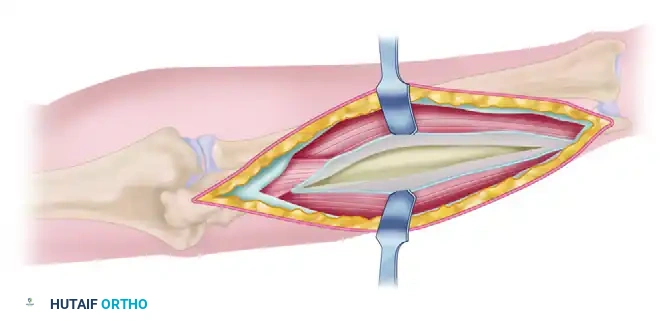

3. Fracture Reduction and Plate Application

The fixation strategy is dictated by the fracture morphology:

- Transverse Fractures: Achieve absolute stability using a 3.5-mm limited-contact dynamic compression plate (LC-DCP). Ensure axial compression is achieved across the fracture site.

- Fractures with a Butterfly Fragment: Anatomically reduce the butterfly fragment and stabilize it with 2.0-mm or 2.4-mm lag screws to convert the complex fracture into a simple one. Follow this with the application of a neutralization plate.

- Oblique Fractures: Reduce the fracture and achieve interfragmentary compression using a 2.0-mm, 2.4-mm, or 2.7-mm lag screw placed perpendicular to the fracture plane. Protect this lag screw with a 3.5-mm limited-contact neutralization plate.

- Extensively Comminuted Fractures: Attempting anatomical reduction of highly comminuted fragments devitalizes the bone and leads to nonunion. Instead, utilize a bridge plating technique. Use a plate of appropriate length to span the zone of comminution, securing it with at least three bicortical screws (six cortices) in the intact proximal and distal segments.

- Note: If the span of the plate on the radius is longer than 6 or 7 holes, adding a lateral contour to the plate is essential to match the native radial bow.

4. Ulnar Fixation and Final Assessment

After the radius is secured, proceed to the ulna using the same plating strategies (compression, neutralization, or bridge plating). Once both bones are rigidly stabilized, assess forearm pronation and supination clinically. The motion should be smooth and unimpeded.

Confirm adequate reduction, restoration of the radial bow, and proper hardware placement with orthogonal fluoroscopy. Ensure no screws are penetrating the radioulnar joints.